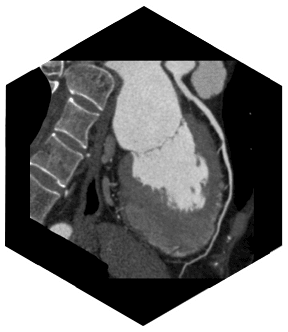

- Интеллектуальная платформа коронарной визуализации мгновенно замораживает сердце и отображает информацию высокого разрешения о сердечно-сосудистых структурах, стентах, кальцификации и бляшках с помощью уникальной интеллектуальной системы управления и алгоритмов коронарной реваскуляризации SinoVision.

- Изображения процесса замораживания коронарной артерии в режиме реального времени